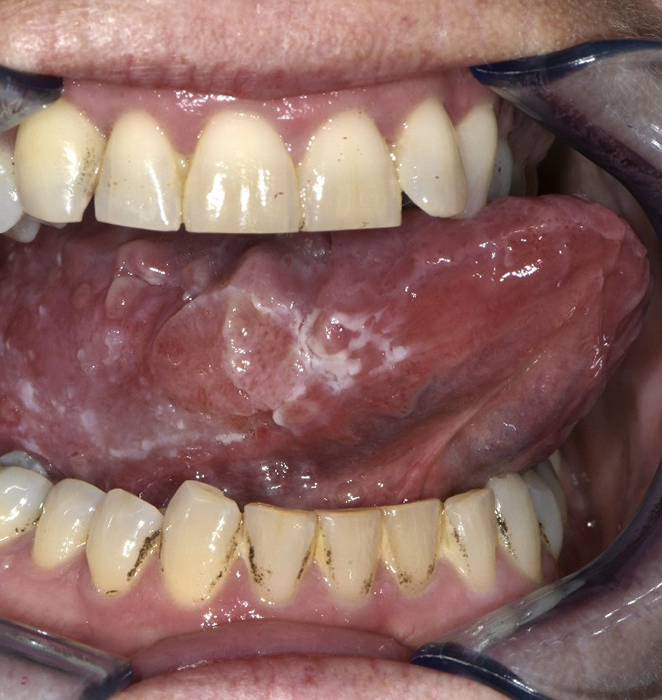

Een 64-jarige vrouw – die minstens 10 jaar mucosale lichen planus heeft (vaginaal en in de mond) – werd verwezen voor een second opinion naar een tertiair dermatologisch centrum voor therapeutisch advies, omdat de plekken in haar mond maar niet rustig werden. Zij werd al behandeld met diprolene gel, triamcinolon in hypromellosezalf, fluticason neusspray, clobetasol oromucosale gel, protopic 0,1% zalf (die ze nu nog steeds gebruikt), ciclosporine mondspoeling en miconazolgel.

Bij lichamelijk onderzoek zagen wij een reticulair netwerk van witte lijnen op beide zijden van de tong. Dit zijn de zogenaamde wickhamstriae die typerend zijn voor lichen planus. Maar wat ons nog meer opviel, was dat er in dat netwerk een lenticulaire papel zichtbaar en voelbaar was, die drukpijnlijk was bij palpatie. Wat is uw diagnose?